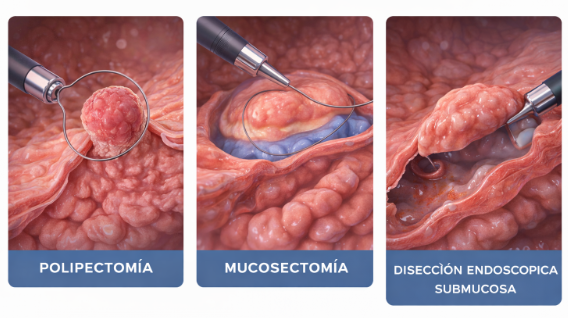

TÉCNICAS DE RESECCIÓN ENDOSCÓPICA:

POLIPECTOMÍA, MUSOSECTOMIA, DISECCIÓN ENDOSCÓPICA SUBMUCOSA

Técnicas avanzadas que permiten extirpar lesiones precancerosas o cánceres tempranos del tracto digestivo, evitando cirugías mayores y preservando el órgano.

Siendo la Disección Endoscópica Submucosa la mas avanzada y técnicamente compleja para tumores malignos tempranos que no invaden capas profundas